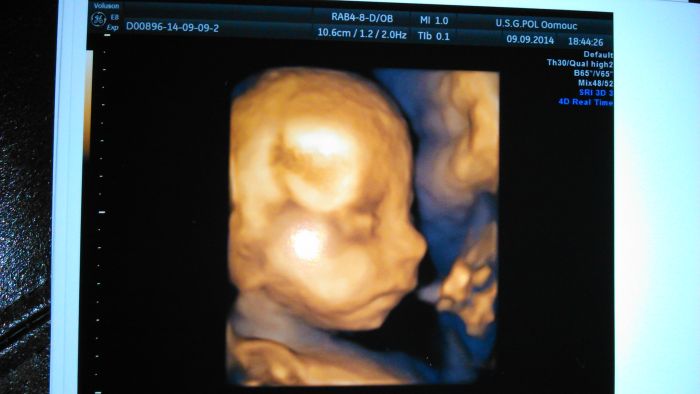

Tak jsme zpátky z 3D UTZ. Potvrdili nám tu holčičku,tak jsem ráda. :-) Je stejná jak naše Marunka. :-)